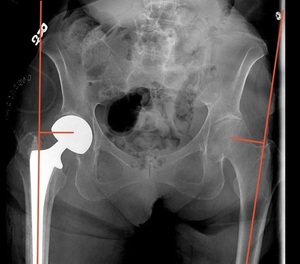

Measurement of LLD was performed using immediate postoperative imaging of an AP pelvis radiograph utilizing the technique described by Ranawat et al.14 This measurement was performed using the difference between a horizontal line drawn from the inferior aspect of the teardrop of the pelvis to a horizontal line drawn from the most prominent aspect of the lesser trochanter. Positive values were given if the length on the operative side is greater than the contralateral side, and negative values were given if the operative side was shorter (Figure 3).

Measurement of FO was also performed using immediate postoperative imaging of an AP pelvis radiograph utilizing the technique described by Asayama et al.15 This technique measures the distance from a vertical line drawn from the center of the femoral head to a line bisecting the femoral shaft. Positive values were given if the operative side had a greater offset than the contralateral side, and negative values were given if the operative side had less offset (Figure 4).